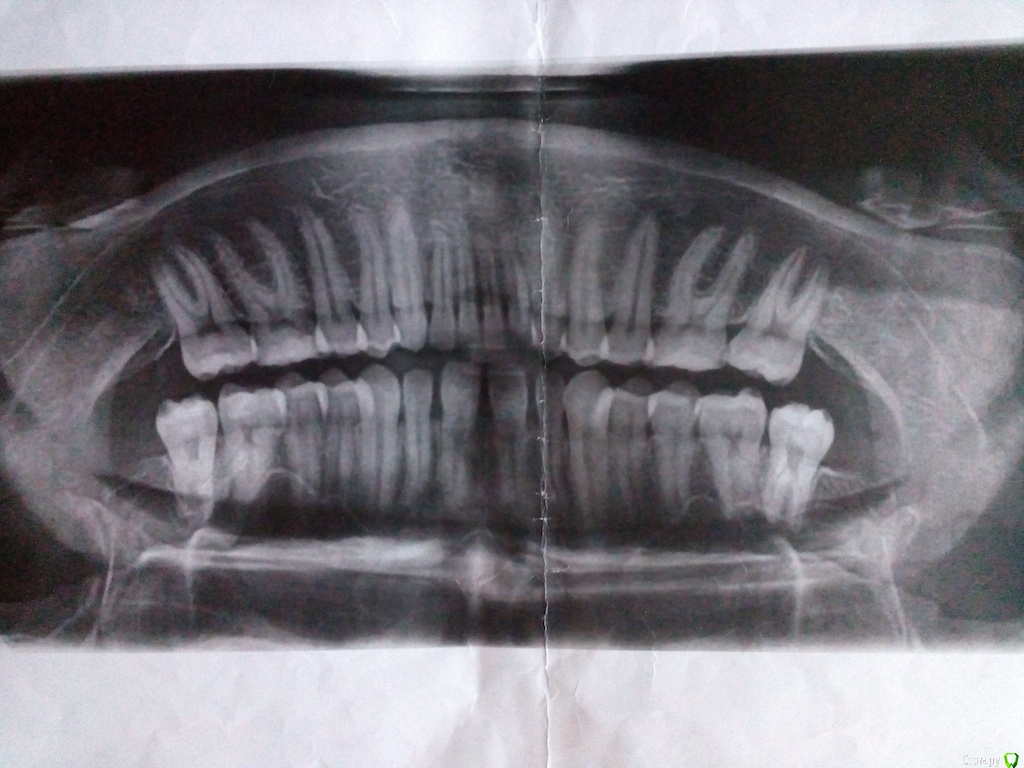

livayi Опубликовано 31 мая, 2015 Автор Поделиться Опубликовано 31 мая, 2015 Прошу прощения за качество фотографий Ссылка на комментарий

livayi Опубликовано 31 мая, 2015 Автор Поделиться Опубликовано 31 мая, 2015 Ортопантомограмма Ссылка на комментарий